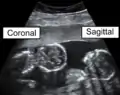

矢状面

矢状面(英語:)是指将躯体纵断为左右两部分的解剖平面[1]。

从中间将躯体分为左右对称两部分的称为正中矢狀面(英語:),其他与正中矢状面平行的矢狀面则称为旁矢状面或侧矢状面(英語:)。